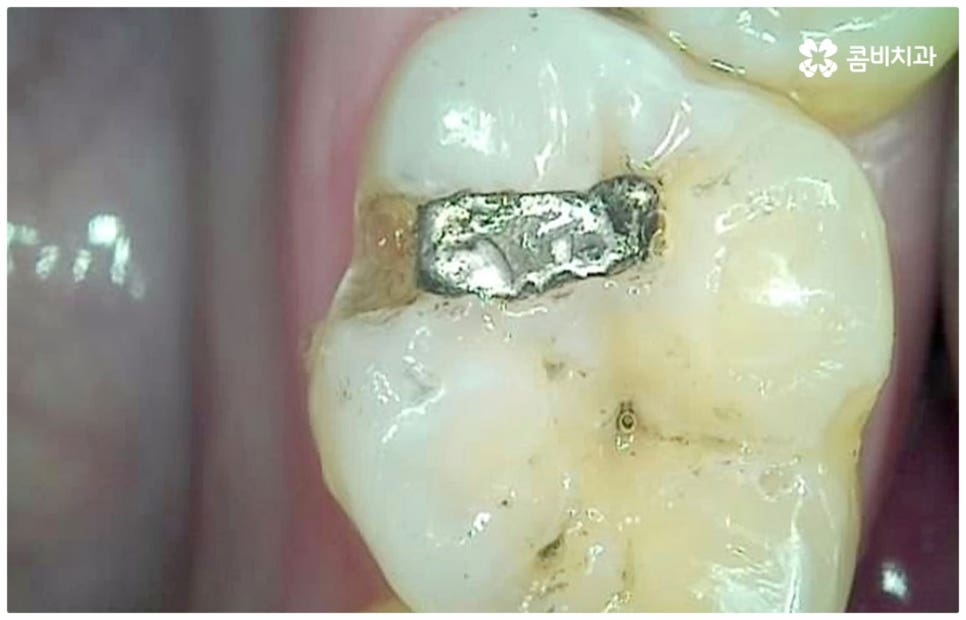

병증이 초기 단계일 때는 치아 겉면인 법랑질이 일부 손상된 것이므로 해당 부위를 긁어낸 후 레진으로 채워주는 비교적 간단한 어금니충치치료 를 해주면 되며 환자분들의 상황에 따라 다르지만 보통 하루 만에 치료가 마무리되는 경우가 많기 때문에 시간과 비용적인 측면에서의 부담도 덜한 편이라고 할 수 있어요. 하지만 법랑질에는 신경이 없기 때문에 초기에는 자각 증상이 거의 없으며 겉으로 드러나는 특징도 두드러지지 않기 때문에 환자분들 입장에서 발견하기가 쉽지 않으므로 주기적으로 검진을 받아 혹시라도 자신이 모르는 사이에 충치가 진행되고 있지는 않은지 꼼꼼하게 살펴보시는 것이 초기 충치에 대처하실 수 있는 지름길이라고 할 수 있습니다.

만약 충치가 어느 정도 진행되어 상아질까지 손상되면 비로소 시리거나 쑤시는 듯한 통증이 생기며 이 때 치과에 내원하시면 정도에 따라 감염 부위를 제거하고 어금니충치치료 방법 중 인레이 또는 온레이를 통해 수복하게 되는데, 이 시기를 지나 병증이 더욱 심해지면 내부 치수조직을 제거하는 신경치료를 진행하게 될 거예요.